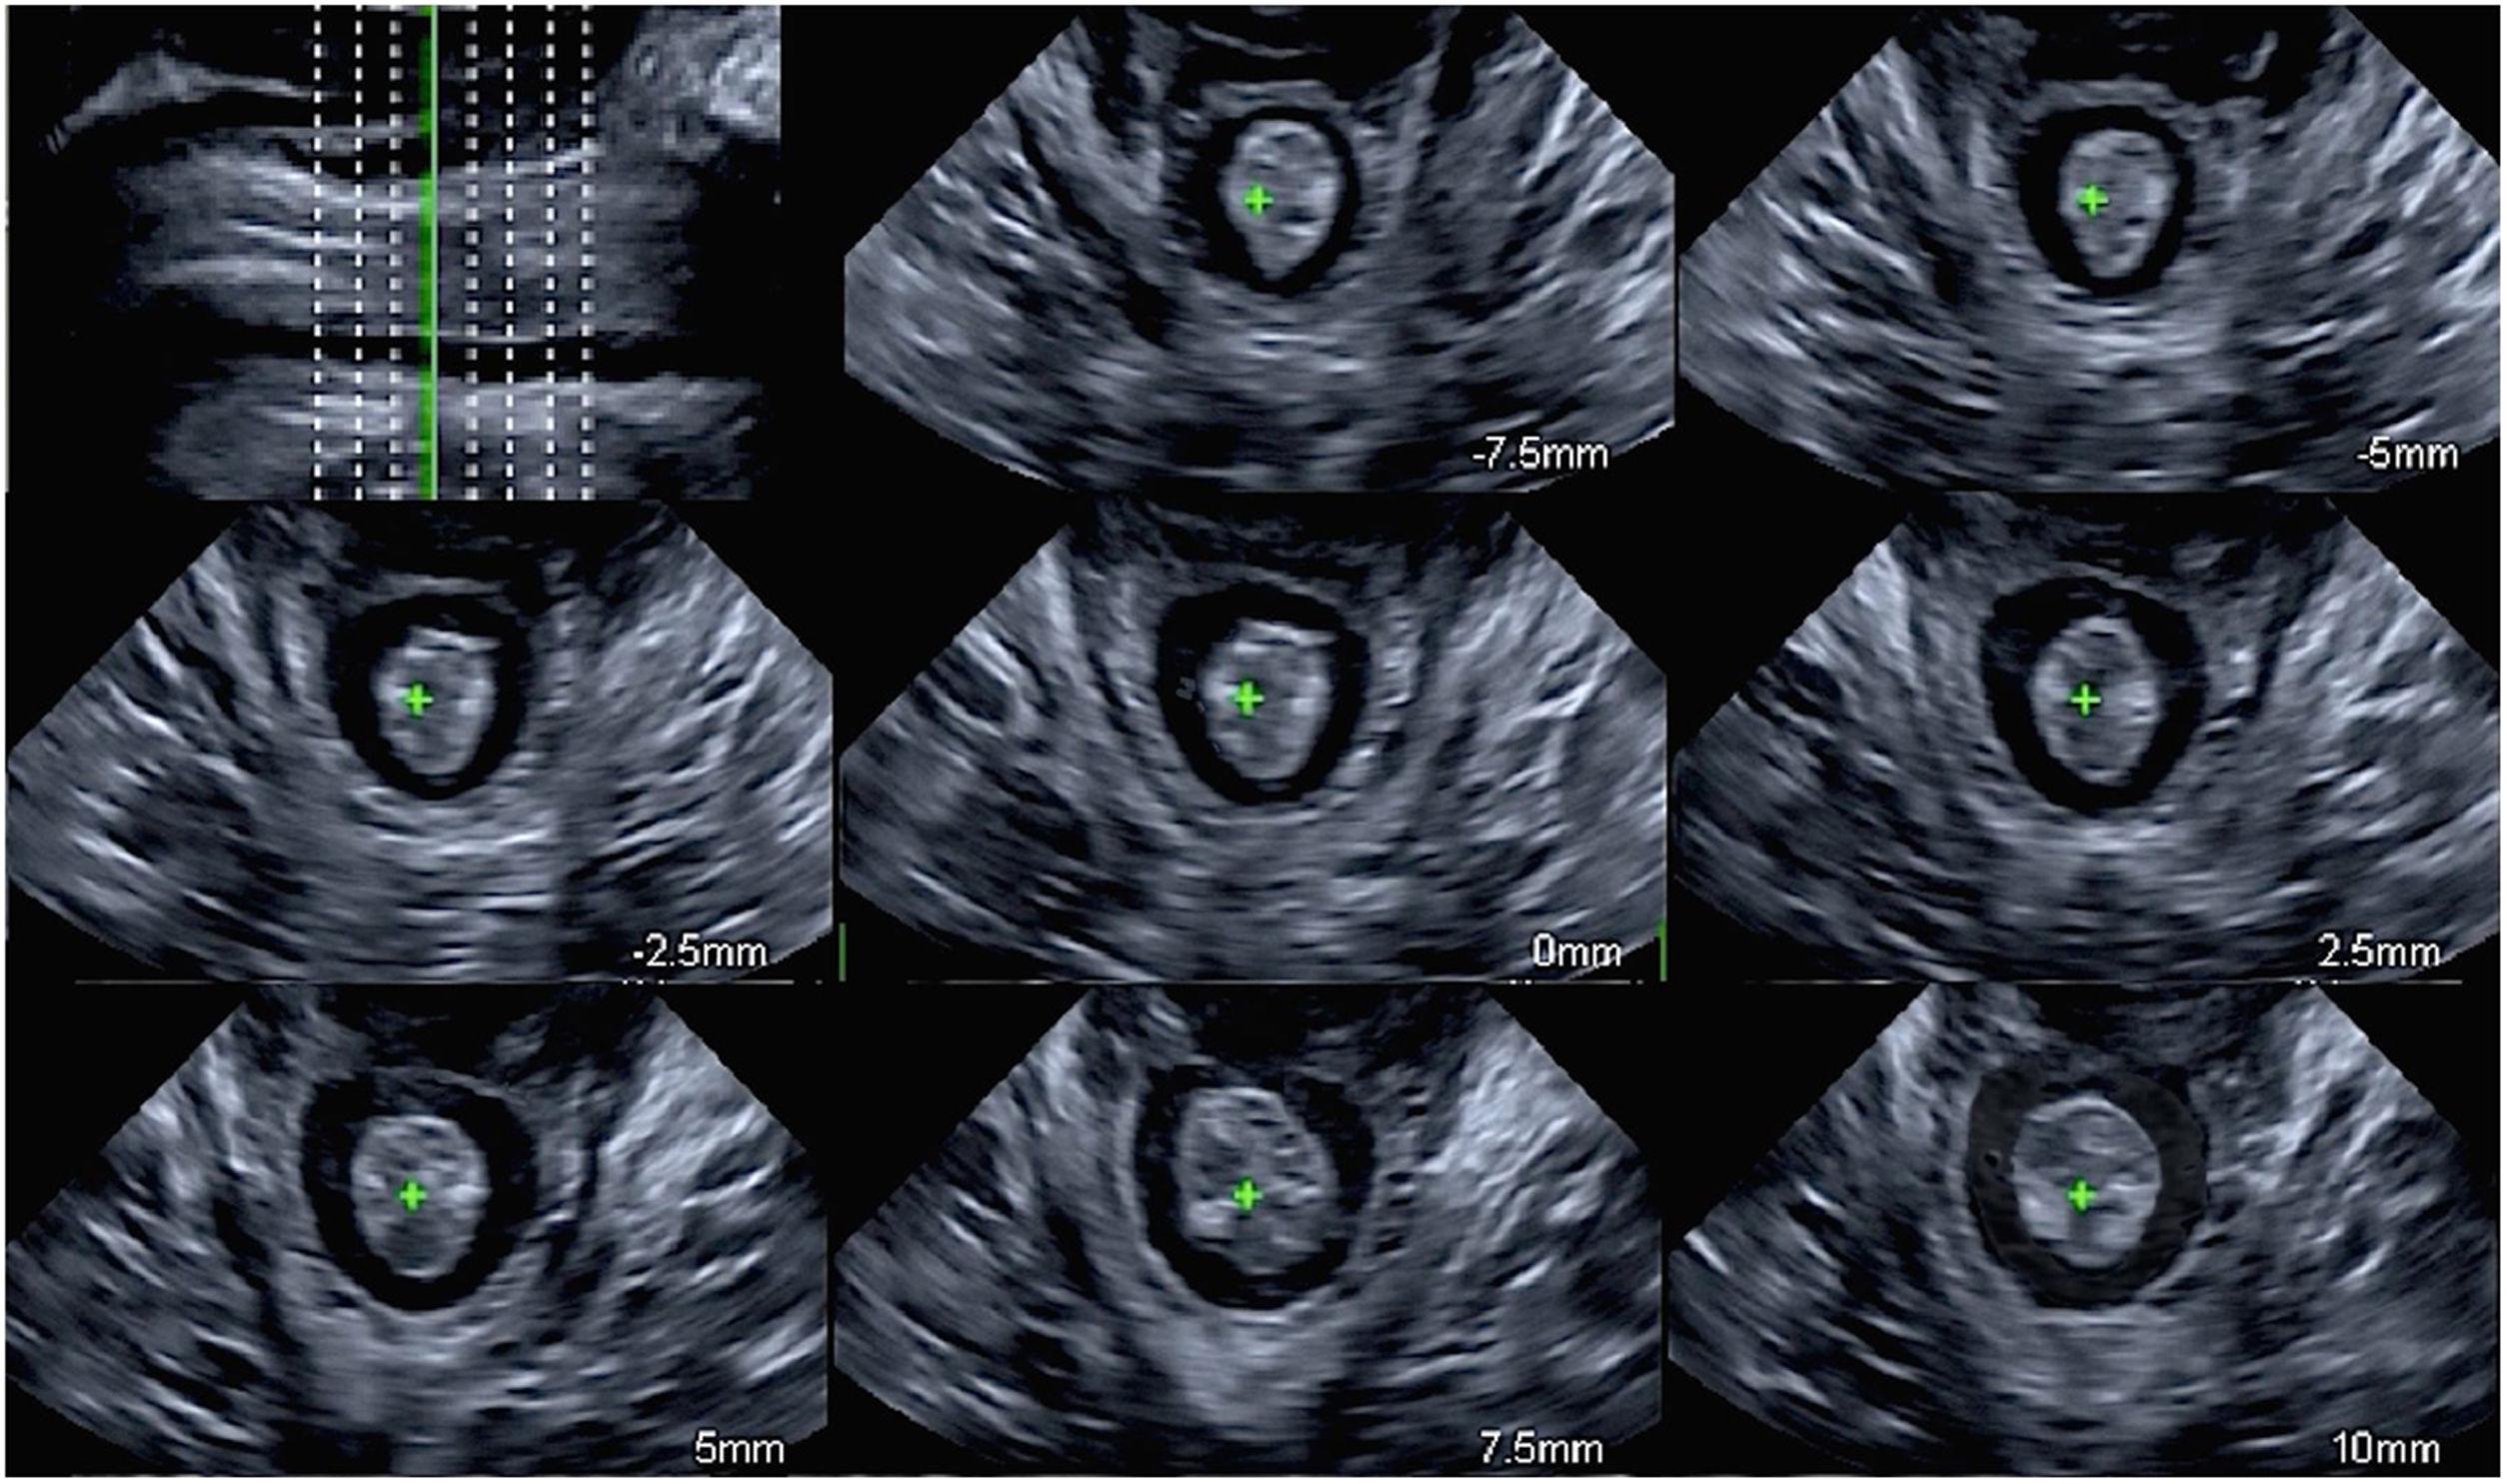

La valoración multicortes del músculo elevador del ano, cuyo objetivo es estudiar la totalidad del músculo, se encuentra estandarizada a partir del PMD. Se obtienen cortes axiales a intervalos de 2,5 mm, correspondiendo a 5 mm en sentido caudal y a 12,5 mm en sentido craneal al PMD, realizando un total de ocho cortes axiales17 (fig. 5). La ubicación exacta de los ocho cortes se establece a partir de los tres cortes centrales, donde el primer corte de la izquierda debe mostrar la sínfisis del pubis abierta, en el siguiente la sínfisis del pubis debe verse cerrada y en el corte de la derecha no debe visualizarse el pubis, siendo reemplazado por un sombreado acústico (fig. 5). La mejor resolución de imagen se logra en contracción máxima aunque el diagnóstico también puede realizarse en reposo13.